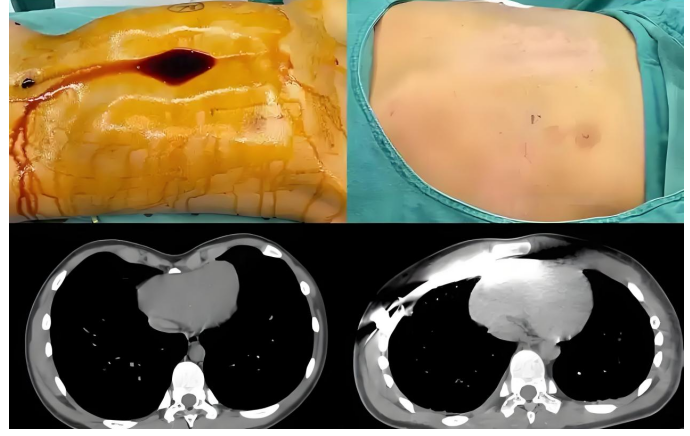

经过充分的术前准备与风险评估,胸外科团队为小文实施漏斗胸矫正手术。手术核心在于通过精准植入矫正钢板,逐步重塑胸廓正常形态,解除对胸腔脏器的压迫。团队凭借丰富的临床经验和娴熟的操作技巧,在保障安全的前提下,精准完成钢板植入操作,最大程度还原胸廓生理结构。

手术过程顺利,术后团队为小文制定了精细化康复护理计划:从伤口护理、疼痛管理到呼吸功能训练、康复锻炼指导。医护人员耐心讲解康复注意事项,手把手指导锻炼方法,家人的悉心照料与小文的坚强意志相互配合,为术后恢复筑牢基础。

在胸外科医护团队的全程守护下,小文的恢复情况稳步推进。随着胸廓形态逐渐改善,他的呼吸越来越顺畅,活动耐力显著提升,曾经因外形问题产生的自卑与焦虑也慢慢消散,性格变得愈发开朗自信。

2025年12月8日,小文再次来到我院,胸外科团队为其实施钢板取出手术。当看到检查报告上“胸廓形态正常、各项指标达标”的结论时,小文和家人脸上露出了久违的灿烂笑容。如今的小文,身姿挺拔、活力满满,彻底摆脱了疾病的束缚,正以崭新的面貌迎接学习与生活的新挑战。